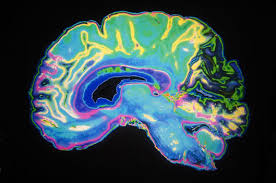

Student Mental Health could also have a connection to future mental health problems when they reach an elderly state such as Alzheimer's. Youth facing challenges in class or at work even in their homes face challenges that they don't realize affect their mental health. Students who spent their time studying and, practicing help build the temporal lobe in the brain. The temporal lobe is a part of the brain known as the limbic system, which includes the hippocampus, the amygdala, the cingulate gyrus, the thalamus, the hypothalamus, the epithalamus, the mammillary body and other organs, many of which are of particular relevance to the processing of memory. Working the mind at a young age is highly beneficial because it helps develop temporal lobe making it easier to remember bits of information that one would usually forget if not for constant studying.

My theory is that education at a young age does affect your chances of getting Alzheimer's when you reach over 40. Youth who don't work their brain by testing themselves or, doing basic mind games to keep the temporal lobe functioning normally is another cause for in the future suffering from Alzheimer’s when they reach 40 and up. Emily Schoenhofen Sharp, M.A. and, Margaret Gatz, Ph.D. both ran studies on this thesis on the relationship between education and dementia.